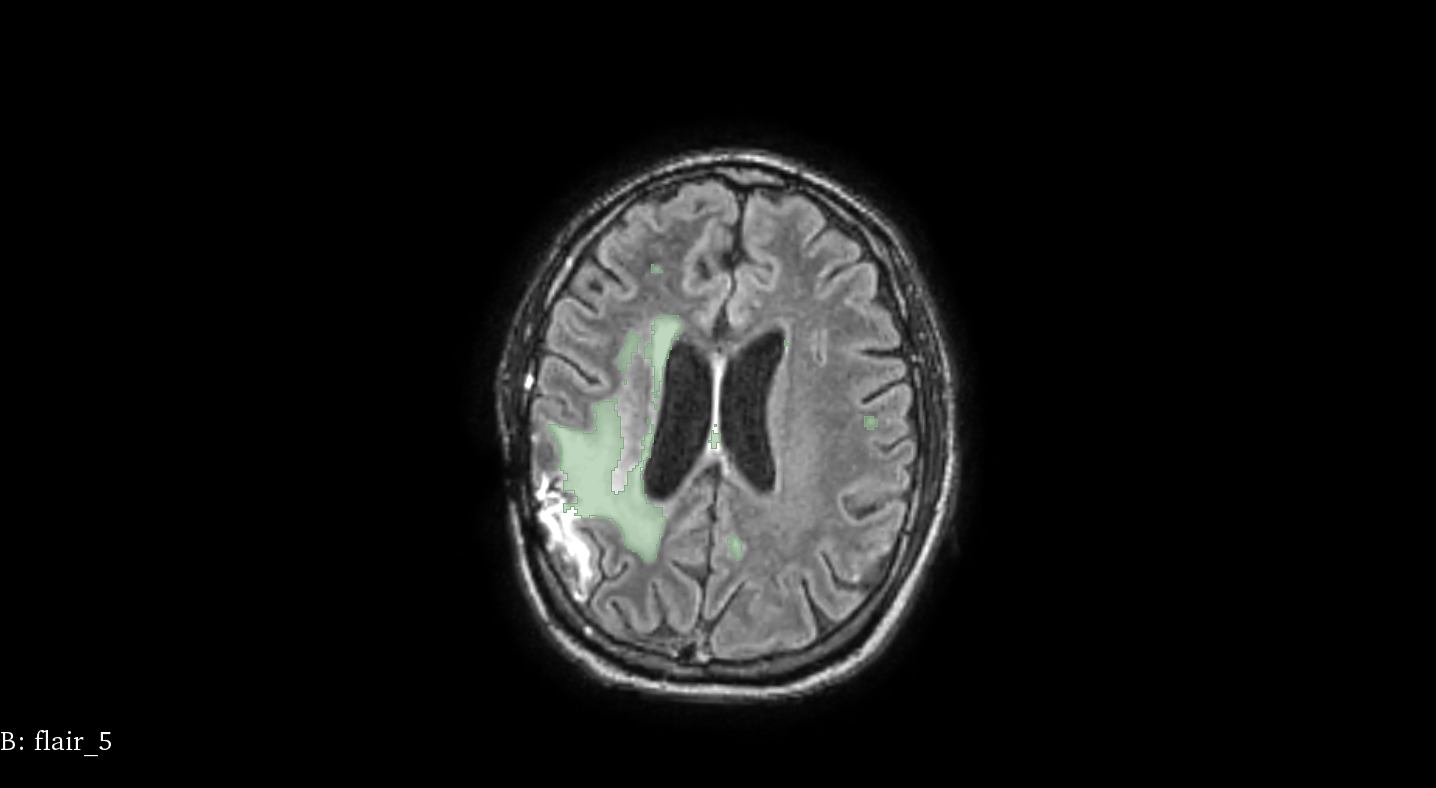

Patient 58

t=

19